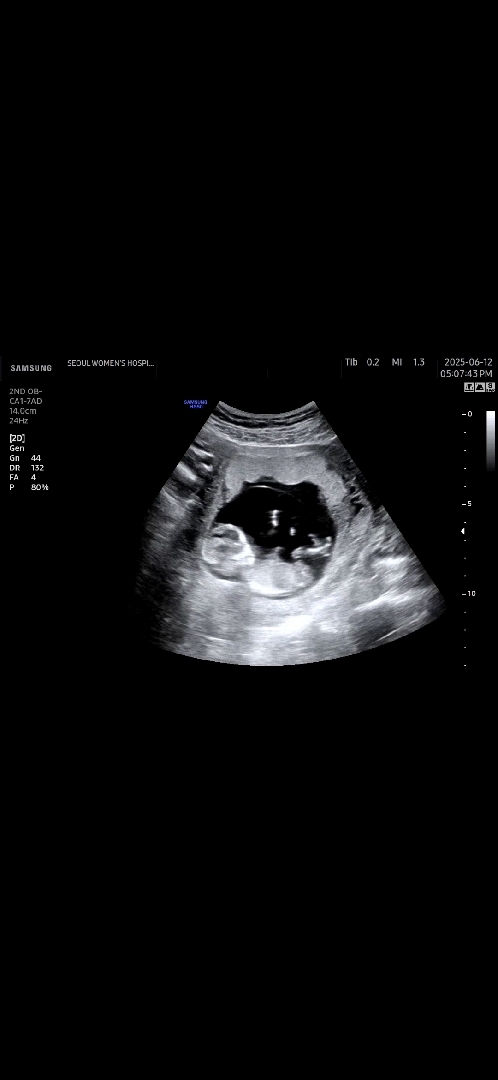

12주 각도법🙏

한달뒤에 병원가는데 넘 궁금해서 올려용 ㅠㅠ 슨생님들 어찌 보이시나요?🥹🙏

딸 한표 드립니다.